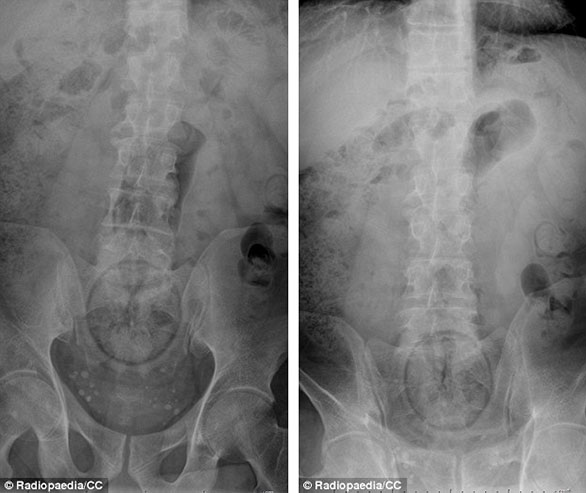

ضم الموقع مجموعة من الصور للأشعة السينية توضح أجساماً غريبة رُصدت داخل أجساد المرضى، ما أثارت دهشة الأطباء الذين قرروا رفعها على موقع طبي متخصص كمادة تعليمية ومرجعية بحثية واستشارية للدارسين في كليات الطب، والذي أنشئ من قبل طبيب أشعة أسترالي عام 2005، بحسب صحيفة دايلي ميل البريطانية.

صورة لأشعة "إكس راي" لأربعيني توضح وجود ما يُشبه "مدقة" طعام بينما يعد وجبة ماليزية.

صورة لأشعة "إكس راي" لمريض دخل معدته برطمان قهوة.